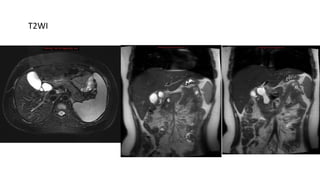

MRI

• T1WI : hypointense dilatation of bile duct

• T2WI : hyperintense

T1WI

T2WI

Type III choledochal cyst in coronal T2WI

MRI • T1WI :hypointense dilatation of bile duct • T2WI : hyperintense

Type III choledochalcyst in coronal T2WI